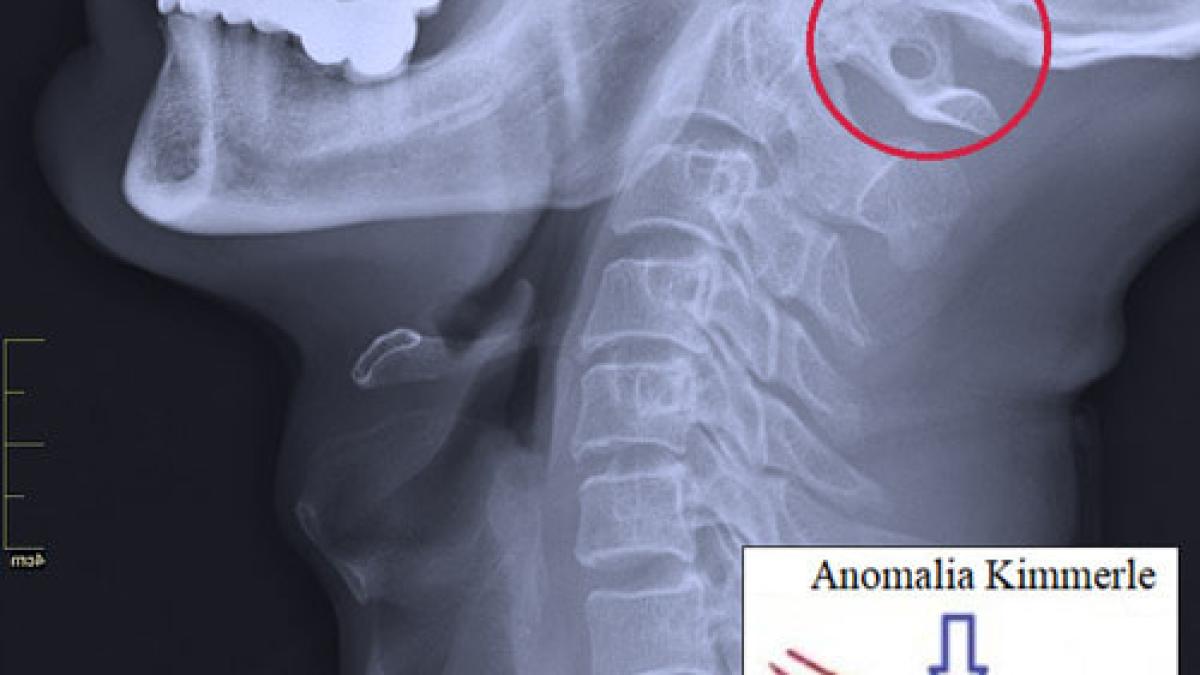

Întâlnită la 12-30% de oameni, această anomalie nu este o maladie, ci de fapt - o variantă anatomică a primei vertebre cervicale (atlasul), produsă din osificarea completă sau incompletă a ligamentului posterior atlanto-occipital peste șantul arterei vertebrale, rezultând în formarea unui foramen arcuat (arc osos suplimentar) care conține artera vertebrală și ramura posterioară a nervului spinal C1, și care poate limita mișcarea (fluxul) arterei vertebrale, provocând sindromul de compresie mecanică a ei.

Un simplu Roentgen al regiunii craniovertebrale, o tomografie computerizată, o angiografie prin rezonanță magnetică, o dopplerografie a vaselor capului și gâtului sau scanarea duplex fac posibilă evidențierea acestei anomalii.